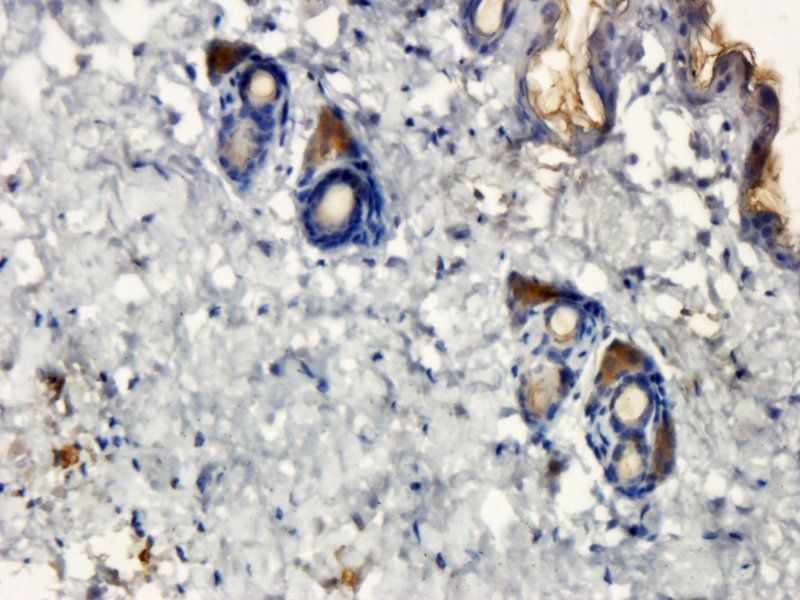

应用稀释比例:IF/ICC: 1:100, IHC-P: 1:200, WB: 1:200-1000

ELISA, ICC, IF, IHC-P, WB